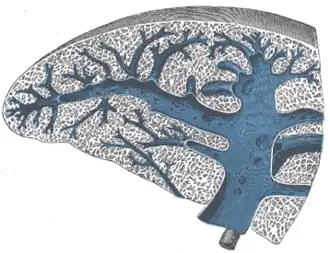

Pulp

Micrograph of splenic tissue showing the red pulp (red), white pulp (blue nuclei in lighter background) and a thickened inflamed capsule (mostly pink – top of image). H&E stain.

The spleen contains two different tissues, white pulp (A) and red pulp (B). The white pulp functions in producing and growing immune and blood cells. The red pulp functions in filtering blood of antigens, microorganisms, and defective or worn-out red blood cells.